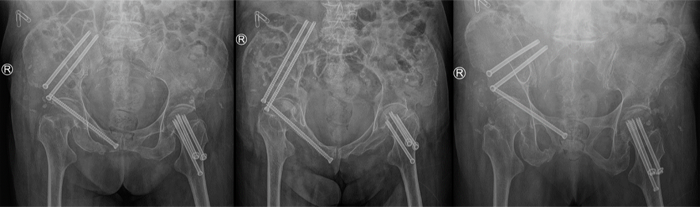

术后X线片

与传统手术相比,智能化骨折复位机器人通过术前自动手术规划、术中3D实时导航可视化、力位协同机器人精准操作,突破了传统手术中医生脑、眼、手的局限,做到了精准、微创、低辐射,成为医生的“超级助手”。国际上专家认为,骨盆骨折通过复位使骨折端的移位能够达到10mm以内即为优良,而智能化骨折复位机器人的复位操作,平均三维精度达到3.41mm,明显优于徒手复位的精度。

机器人对于高龄骨折患者有突出优势。2022年,一位92岁的老人不慎骨盆骨折。老人伴有多种内科疾病,同时有严重的骨质疏松,使用传统大的切开复位手术,老人家身体吃不消,很容易过不了手术这一关。如果选择卧床保守治疗,结果往往会更糟。经过多科室会诊和详细的术前计划,吴新宝团队决定使用骨折复位机器人实施微创手术,利用机器人结构优势,实现移位骨折有效、稳定的把持;利用系统的智能化复位功能,实现骨折的良好复位,同时使用自行开发的加长全螺纹螺钉对骨折实施微创的稳定固定。术后,老人很快借助辅助装置开始下地行走训练,拍片显示骨折复位非常好。这位92岁的老人,是吴新宝团队成功开展机器人微创复位治疗中年龄最大的患者。在临床研究中,吴新宝团队对多名80岁以上的高龄患者成功实施了机器人手术治疗,化解了高龄骨盆骨折微创治疗的难点,突破了骨折复位机器人在临床使用的新高度,为无数患者带来了新希望。2022年,智能化骨折复位机器人入选国家药监局创新医疗器械特别审查通道,并在全国6家医院开始多中心注册临床试验。2023年初已完成全部注册临床试验病例入组。